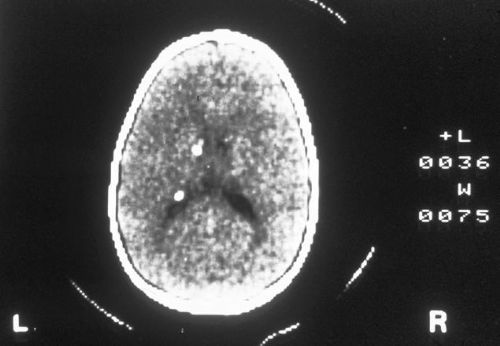

Diagnosis?

Candlewax calcification

= tuberous sclerosis